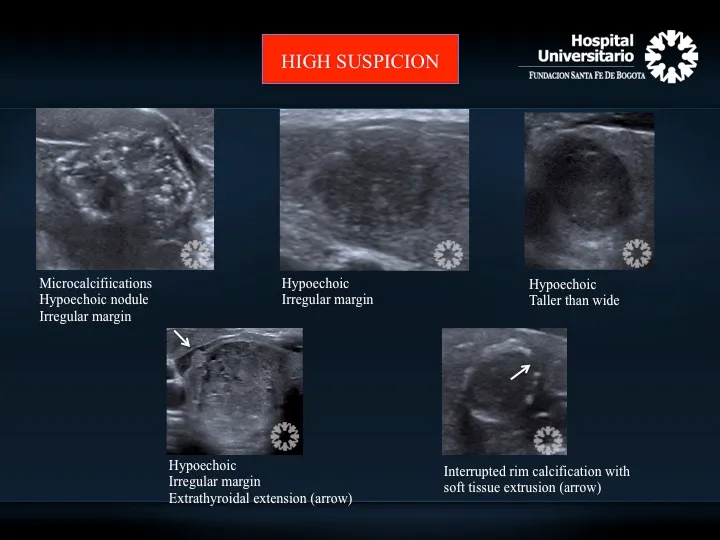

- ⚠️ Suspicious US features: Microcalcifications, hypoechogenicity, irregular margins, taller-than-wide.